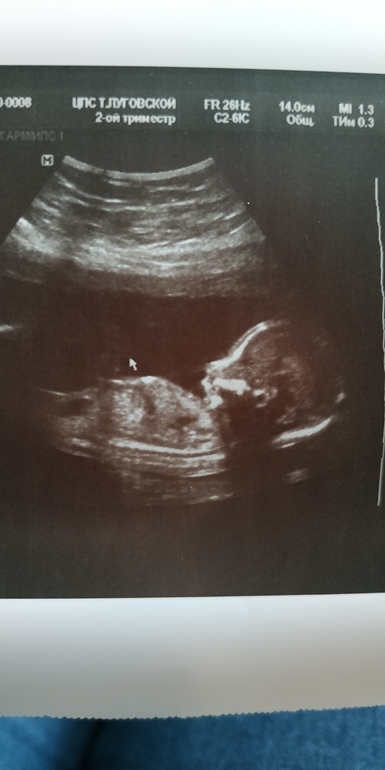

Второй скрининг

Наши будни, наши неделькиБыла на скрининге почти 2 недели назад и только руки дошли сюда написать..У нас всё отлично) все органы в порядке) И у нас вторая девочка 💕💕💕 наша красотуля снова закрывала личико ладошками- стесняшка 😅 Толкается во всю.. Первые шевеления ощутила снова рано- в 14 недель.. Маруську почувствовала в 15) Папа всё нервничает, не может определиться с именем) пока у нас лидирует Анастасия..посмотрим;)